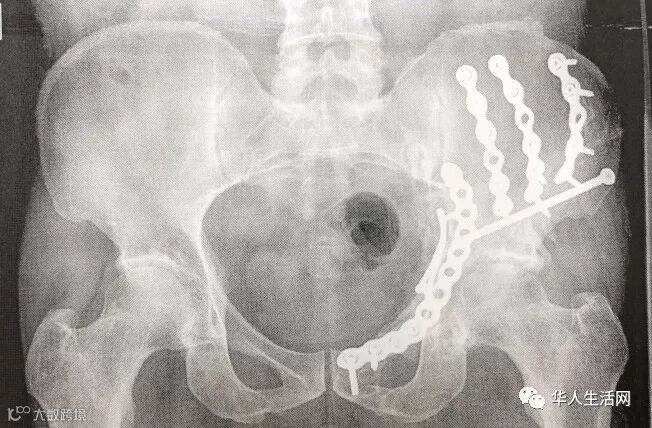

陈先生表示,2014年6月19日下午5时左右,他在皇后区艾姆赫斯特(Elmhurst)的一个商住两用建案的建筑工地工作时,从一个梯子上摔下来,导致胯部骨折。在艾姆赫斯特医院接受一个大手术,并住院20天。“我的家人都在中国,出事后我不能工作,没了收入,只能借钱生活。”